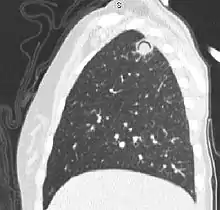

Sagittal reformat from a CT scan of the chest showing air crescent sign in a patient with invasive fungal infection. There is a rounded cavity in the apical right upper lobe, with a non-dependant soft-tissue nodule within it. Also there is some subtle ground-glass opacity surrounding the lesion.